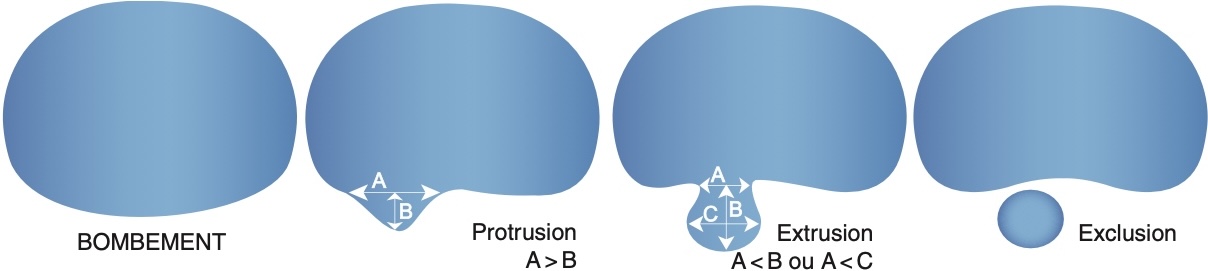

vocabulaire = migration craniale/caudale; fragment exclu épidural

vocabulaire = migration craniale/caudale; fragment exclu épidural